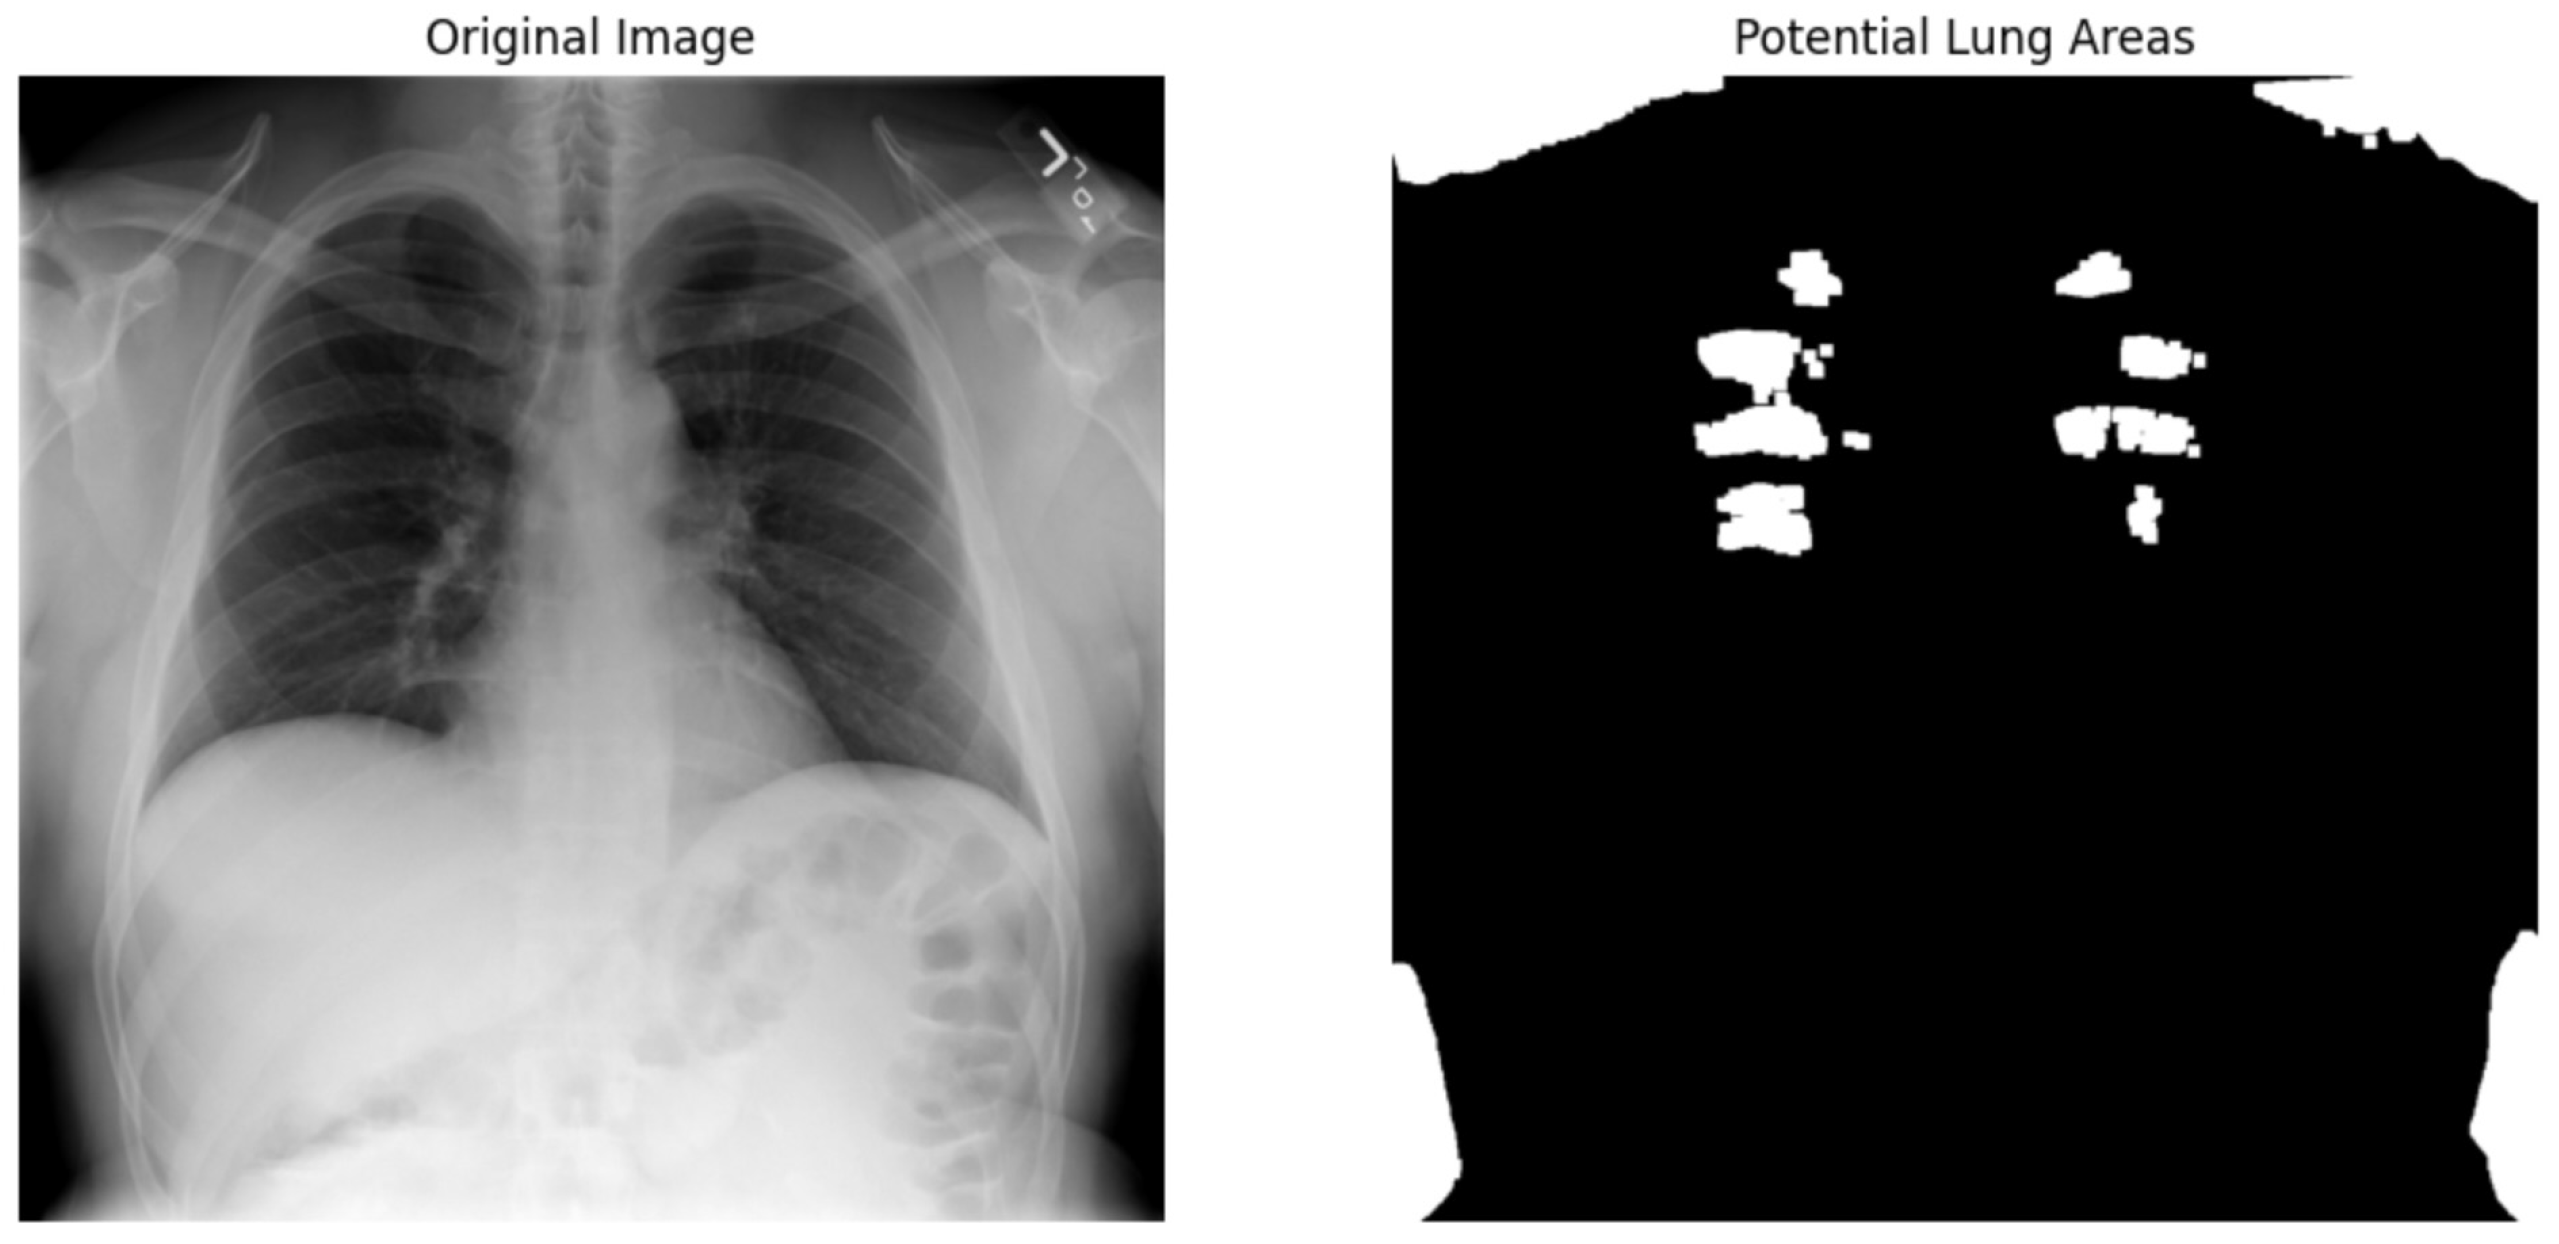

We used the ResNet50 algorithm for feature extraction and compared to other architectures like DenseNet121. Figure 12 ResNet50 employs residual learning with deep residual networks, effectively mitigating the precision of feature maps, which are critical for accurate segmentation and diagnosis in clinical settings. On the other hand, while DenseNet121 is lauded for its feature reuse capabilities and potentially lower model complexity due to fewer parameters, ResNet50’s streamlined data flow and gradient propagation provided a more robust framework for capturing and emphasizing relevant features in chest X-rays. It is crucial for detecting and diagnosing diverse and minute pathological changes within the lungs, offering profound insights into pulmonary conditions in medical imaging. Chest X-ray potential area mark in Figure 13 followed binary thresholding techniques in processing a chest X-ray image to isolate potential lung areas from the surrounding anatomical structures. Binary thresholding is a form of image segmentation that involves converting a grayscale image into a binary image, where each pixel is assigned a value of either 0 or 1 (black or white). The binary thresholding algorithm is particularly effective for enhancing lung tissue visibility against other body components by setting a pixel intensity threshold. Applying such a threshold highlights areas within the lungs that exceed a certain intensity level (shown in white), while less relevant areas remain black. This technique simplifies the image, allowing for clearer identification and analysis of lung regions that could contain pathological features. It aids in detecting anomalies like fluid build-up, masses, or unusual opacities that might indicate conditions such as pneumonia, tuberculosis, or lung cancer. ResNet architecture parameter in Table 8 and Table 9.

We applied scientific analysis on a random 7 sample, which was provided by the clinical specialist. The LIME Analysis for Image Data (a), (b), (c), (d), (e), and (f) is in Figure 22, Figure 23, Figure 24, Figure 25, Figure 26 and Figure 27. There are two parts of LIME analysis from the provided chest X-ray images to detect the disease area. Original Image and LIME explanation;

• Original Image: The patient’s thoracic cavity. It displays the typical anatomical structures of the chest, including the lungs, ribs, and heart.

• LIME Explanation: The result of applying LIME to the chest X-ray image. The yellow boundaries indicate the regions of the image that were most influential in the model’s decision-making process when determining whether the image indicated a particular condition. In this context, these regions are the parts of the X-ray that the AI model considered most important for making its diagnostic prediction.

The analysis very useful for clinicians to understand the model’s behavior and ensure that it aligns with medical expertise. The use of LIME helps in making the AI model’s interpretability decisions more transparent and interpretable. It allows medical professionals to verify whether the AI’s focus areas correspond to clinically significant regions. It also enhanced diagnostic capability of understanding which parts of the images in the AI model in refining the model further and ensures that it makes accurate and reliable predictions. This is particularly crucial in medical diagnostics where interpretability and accuracy are paramount.